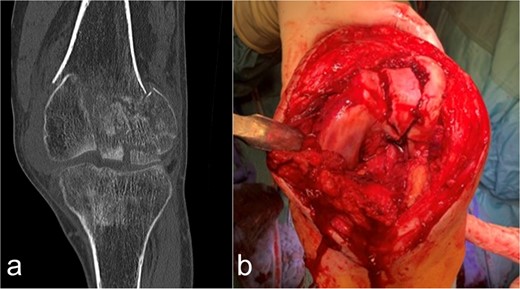

In the 48-year-old man with a body mass index of 18.4 kg/m2, after initial treatment in the emergency room, conventional imaging and CT examination revealed a supra-intracondylar multiple fragment fracture of the femoral bone (33C3. 2) (Fig. 1a), a subcapital dislocated humerus fracture (11C3.1), a radius fracture with involvement of the caput and collum radii (2R1C3 and Mason stages II and III) and a distal tibia with Maisonneuve fracture (44C2.2 and Weber C). The fracture classification was based on the AO-Trauma International Board & the Orthopedic Trauma Association [6].

Case presentation of the knee region. (a) The coronal CT segment shows a transcondylar multifragment fracture of the femoral bone. (b) The intraoperative situs shows the comminuted zone of the condylar articular surface.

Osteosynthetic treatment via an open approach to the knee joint presented the multifragmentary femoral fracture radiating into the joint with an osseous avulsion of the lateral collateral ligament and posterolateral insertion of the anterior cruciate ligament (Fig. 1b). After reduction of the fracture fragments with temporary fixation using K-wires, an LCP 6-hole plate (Synthes®) was positioned medially and a 7-hole LISS plate (Synthes®) laterally and anchored with multiple screws (Fig. 2a and b). The osseous avulsion of the anterior cruciate ligament was fixed with a 3.5-mm SharkScrew®, the avulsion of the lateral collateral ligament with two FibreWire Loops®.